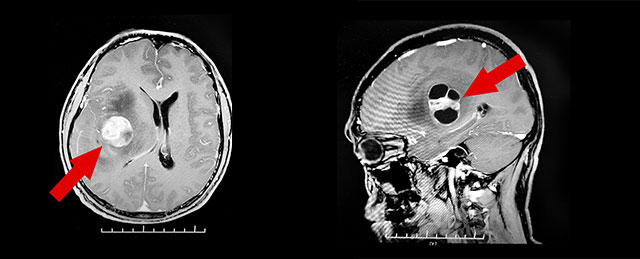

PET/CT检查,结果显示:右侧额顶叶岛叶见团片混合密度灶。头颅增强磁共振检查发现,右侧颞岛叶团块状囊实样占位,病灶大小约2.9*2.5*3.9cm,毗邻右侧侧脑室及第三脑室受压变窄、左侧偏移。结合病灶影像特点,考虑为胶质瘤可能性大。

▲右侧颞岛叶团块状囊实样占位